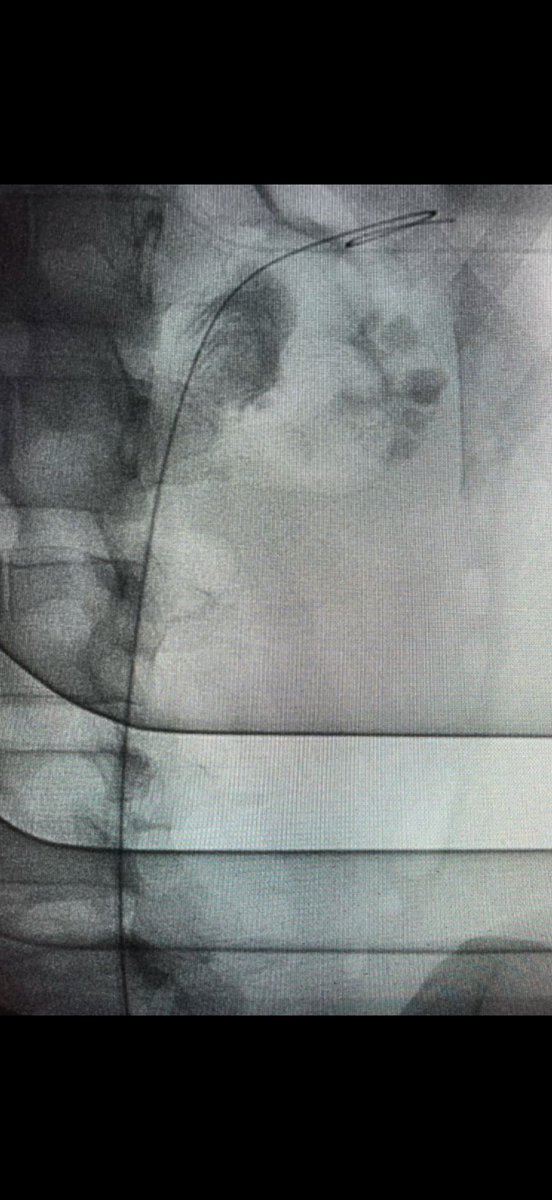

Guido Giusti@GuidoGiusti·

Before leaving to Madrid for the big #EAU25 meeting, Im more than happy to supervise @_FDeLeonardis performing a #SUPINEPCNL with both rigid & flexy scope. I also underline the fact that it’s me irrigating as a resident with my #Tflow system! ….. it is not true that #PCNL is so difficult… but adequate training is crucial !!! #ETCE

Guido Giusti tweet mediaGuido Giusti tweet media